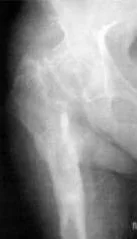

Как видно на приведенной рентгенограмме, после удаления эндопротеза остаётся "пустое место" в области бывшего тазобедренного сустава.

При стоянии или ходьбе на эндопротез ложится большая нагрузка, в соединении между костью и эндопротезом происходят микродвижения. Вследствие этого эндопротез расшатывается. Может расшататься как ножка (бедренный компонент), так и чашка (вертлужный компонент) протеза. Ножка эндопротеза может разрушить стенку кости, в которой расположена - возникает перипротезный (парапротезный) перелом.

При перипротезном переломе потребуется операция остеосинтеза с последующим длительным ограничением физической активности.